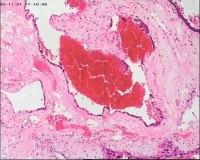

性别

女

年龄

20岁

停经3月,阴道不规则流血7天。

宫刮物

灰白灰红碎组织一堆,大小为7*6*1cm,部分组织呈水泡状

水肿的绒毛和蜕膜,没看到增生的滋养细胞。必要时可做IHC除外部分葡萄胎,并结合临床HCG。

考虑葡萄胎